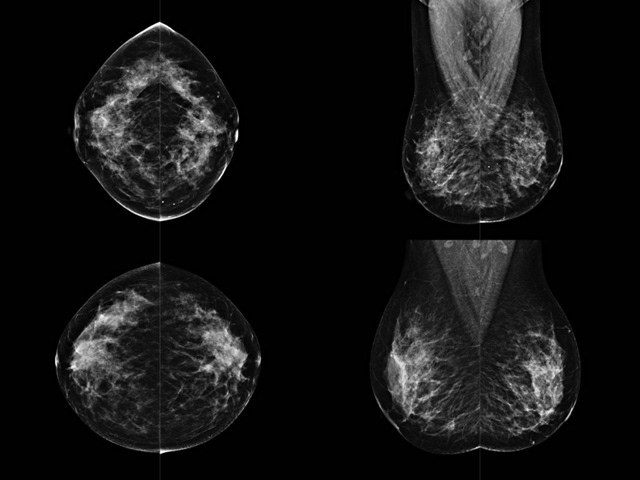

乳腺DR成像設備中非晶硅跟非晶硒兩種平板探測器

乳腺DR成像設備中非晶硅跟非晶硒兩種平板探測器。更要提供優(yōu)質(zhì)的圖像質(zhì)量乳腺的組織結構與厚度各不相同,減少重拍率輻射劑量,,乳腺的主要構成組織均為軟組織結構,組織之間密度十分相似,缺乏天然對比度。選擇軟X線攝影技術獲得良好對比度的乳腺結構影像。增加各組織對X線的吸收差異。乳腺攝影測和分類,平板探測器的像素尺寸范圍應在50到100μm之間。特別是微鈣化灶可以小到100到200μm,平板探測器都必極小微鈣化灶進行成像。

乳腺DR是利用X光來做檢查,在一瞬間將被檢測到的位置投影出來,因為是瞬間的輻射,所以只需要0.5秒的時間。因此對病人的輻射很低,大約是0.023mSv,比國家的標準要低得多。DR系統(tǒng)由 X線、發(fā)生裝置、直接轉換平板探測器、系統(tǒng)控制器、影像監(jiān)視器、影像處理工作站等組成。能檢查胸腔積液、肺結核、大葉性肺炎、肋骨骨折等。心室增大、主動脈擴張、主動脈瘤等心臟病。腹部病變,如腸梗阻、腸穿孔等,DR上可見液氣平面、膈下游離氣腫。DR表現(xiàn)不正常,要結合臨床表現(xiàn)、體征、癥狀等綜合分析,結合CT、彩超、血液分析等,才能作出正確的判斷。